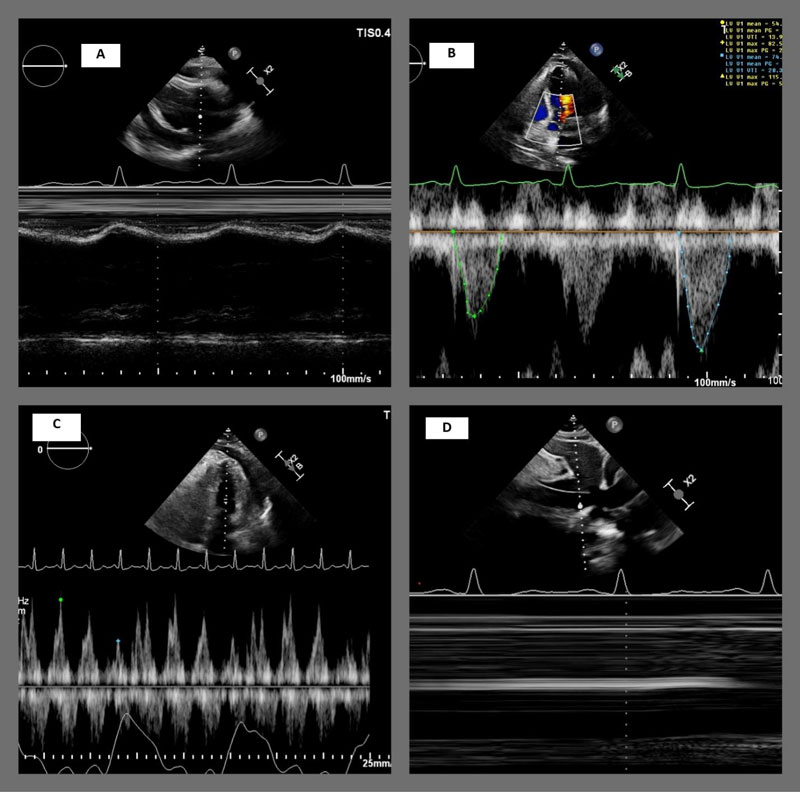

The patient was placed under conscious sedation with continuous hemodynamic monitoring. Fluoroscopic and ultrasound-guided pericardiocentesis was performed, yielding 800 mL of brown-colored pericardial fluid, and a pigtail catheter was placed for continued drainage. Postoperatively, continuous hemodynamic monitoring demonstrated resolution of tachycardia and normalization of blood pressure. Over the following two days, the drainage output gradually decreased to less than 50 mL. A follow-up echocardiogram two days later demonstrated residual loculated pericardial effusion, pericardial thickening with septal bouncing, and Doppler findings suggested possible constrictive pericarditis (Figure 2).

Figure 2

Figure 2 (A) M-mode in PLAX view showing Early RV diastolic collapse, blue arrow. (B) PW Doppler sample on the LVOT showing significant stroke volume variation consistent with tamponade physiology. (C) PW Doppler sample on the mitral inflow showing significant respiratory variation consistent with tamponade physiology. (D) M-mode on the IVC showing plethoric non collapsible IVC variation consistent with tamponade physiology.